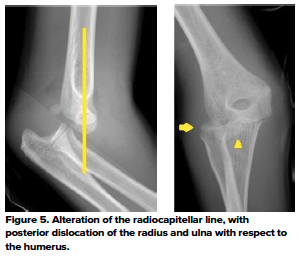

The anterior humeral and radiocapitellar lines are used to assess elbow alignment. The lines assess the geometric relationship of one bone to the other. Malalignment usually indicates fractures.

The radiocapitellar line evaluates the relationship of the proximal radius to the capitellum on all views (Fig 4). If the integrity of this line is compromised, then dislocation should be suspected (Fig 5)